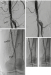

Abbildung 1: Stenosen (a): Multiple, hochgradig verkalkte, teils subokklusive Stenosen der distalen AFS (Pfeile) und der AP (Pfeilspitze); (b): Nach Atherektomie mittels Jetstream (2,4/3,4 mm) und DEB-Angioplastie zufriedenstellendes Ergebnis aller Läsionen. Auf eine Stentimplantation konnte verzichtet werden |

(a): Multiple, hochgradig verkalkte, teils subokklusive Stenosen der distalen AFS (Pfeile) und der AP (Pfeilspitze); (b): Nach Atherektomie mittels Jetstream (2,4/3,4 mm) und DEB-Angioplastie zufriedenstellendes Ergebnis aller Läsionen. Auf eine Stentimplantation konnte verzichtet werden |